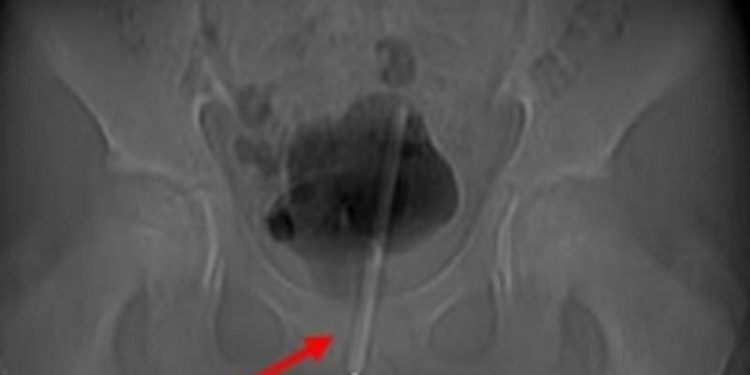

Çekilen röntgen, termometrenin idrar yoluna kadar sokulduğunu ve çocuğun mesanesine girdiğini ortaya çıkardı.